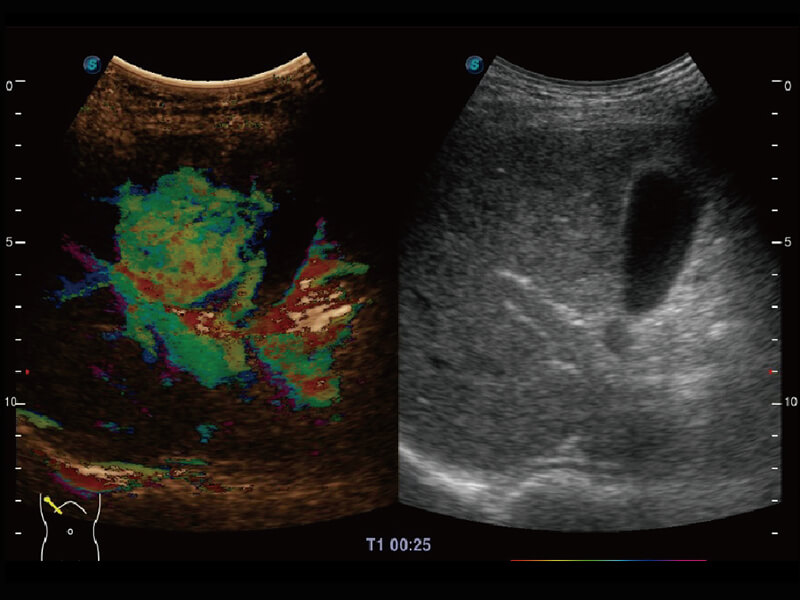

彩色多普勒超声诊断系统

成像功能

性能优异的硬件架构,极大提升超声系统的运行效率和数据处理能力。相比以往超声成像系统,Wis+平台为您带来极快的响应速度和成像帧频,提升检查流畅度。

S60探头工艺,从前端信号处理每一个环节采集无损声学数据,真实还原组织原貌,再现解剖细节。

超宽频带技术,为容积成像带来优质的二维图像基础,为您呈现丰富的结构细节,栩栩如生地展示宝宝的宫内形态以及各种组织的立体结构。